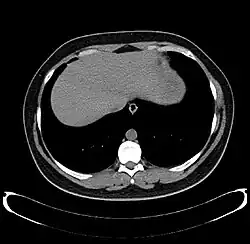

Development

CT scan showing an adult liver in the axial plane

Organogenesis, the development of the organs, takes place from the third to the eighth week during embryonic development. The origins of the liver lie in both the ventral portion of the foregut endoderm (endoderm being one of the three embryonic germ layers) and the constituents of the adjacent septum transversum mesenchyme. In the human embryo, the hepatic diverticulum is the tube of endoderm that extends out from the foregut into the surrounding mesenchyme. The mesenchyme of septum transversum induces this endoderm to proliferate, to branch, and to form the glandular epithelium of the liver. A portion of the hepatic diverticulum (that region closest to the digestive tube) continues to function as the drainage duct of the liver, and a branch from this duct produces the gallbladder.[37] Besides signals from the septum transversum mesenchyme, fibroblast growth factor from the developing heart also contributes to hepatic competence, along with retinoic acid emanating from the lateral plate mesoderm. The hepatic endodermal cells undergo a morphological transition from columnar to pseudostratified resulting in thickening into the early liver bud. Their expansion forms a population of the bipotential hepatoblasts.[38] Hepatic stellate cells are derived from mesenchyme.[39]